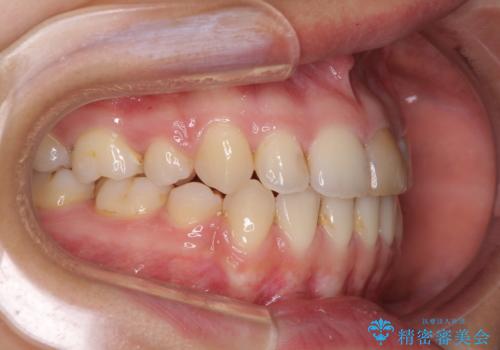

- 上の八重歯を気にして来院された患者様です。

受け口傾向にあるため、上顎前歯の叢生解消とともに下顎前歯を後方へ移動させることを目的とし、上下左右の第一小臼歯4歯を抜歯することとしました。